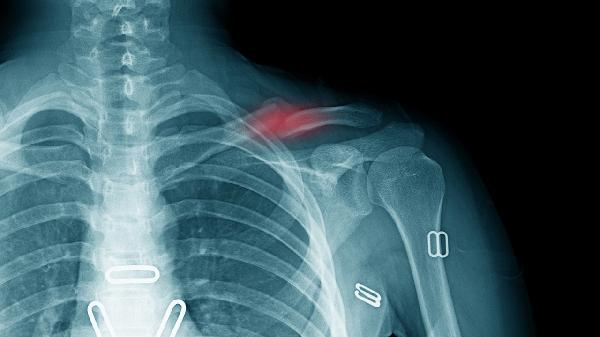

胸外科侧重胸壁及肺部病变。胸膜炎常由感染或肿瘤引发,伴随呼吸加重疼痛,需通过胸部X线或CT明确。自发性气胸突发锐痛伴呼吸困难,胸部影像学可确诊。肋软骨炎表现为局部压痛,通常通过触诊和排除性检查诊断。